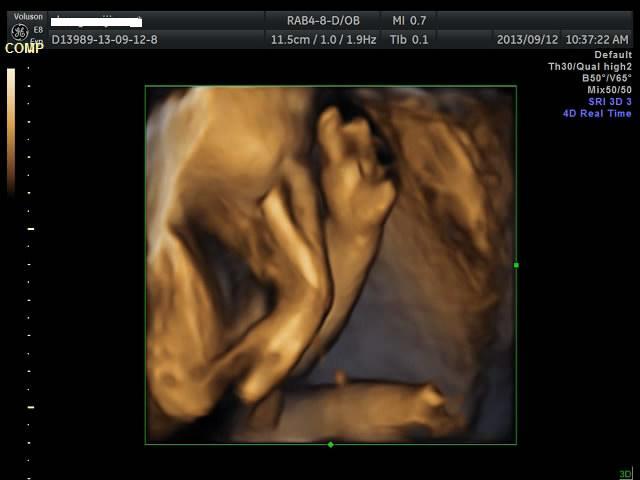

有没有能够帮我看看是千金还是帅哥的朋友?只是好奇是应该准备蓝色衣服还是应该买粉色衣服呢? 点击展开 匿名用户 2013-09-12 20:44 为您推荐: 其他回答 吓死我了... 匿名用户 2013-09-12 20:57 看不出来啊,买米黄色的吧 不论男女,都很好看 匿名用户 2013-09-12 20:57 帅哥的朋友吧,最好选粉红色的 匿名用户 2013-09-12 20:53 要怎么看才好 匿名用户 2013-09-12 20:48 千金,买粉红的 匿名用户 2013-09-12 20:47 相关问题 谁帮我看看是千金还是帅哥! 来看看我家24天的小帅哥,穿粉色衣服么么哒 张凡帅吗?很好奇听说是个帅哥,求解!!!!!!!